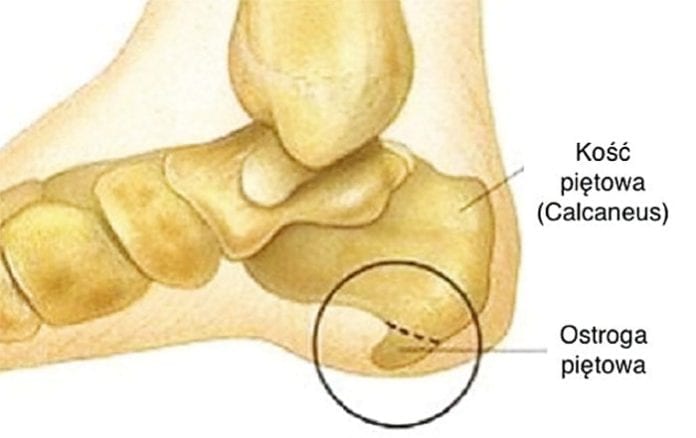

Ostroga piętowa inaczej zapalenie rozcięgna podeszwowego. Bezpośrednią przyczyną powstania ostrogi piętowej jest zapalenie, powstające w miejscu złączenia kości pięty z rozcięgnem piętowym. Jest to struktura, która ulega ciągłemu napinaniu i rozluźnianiu się przy każdym kroku.

Pierwszym krokiem w procesie leczenia ostrogi piętowej jest udanie się do lekarza, aby potwierdzić bądź wykluczyć diagnozę. Leczenie ostrogi piętowej zwykle przebiega w podobny sposób. Pacjent poddawany jest serii zabiegów fizykoterapeutycznych (na przykład ultradźwięki, jonoforeza, laseroterapia, krioterapia, kinezyterapia miejscowa, czy fala uderzeniowa). Również zalecane i bardzo pomocne w uśmierzaniu uciążliwego bólu są masaże stóp jak również ćwiczenia i delikatne rozciąganie, które zaleci fizjoterapeuta. Istotne dla skuteczności leczenia jest, aby zabiegi wykonywać w całej serii. Nawet w momencie ustania bólu i pozostałych dolegliwości przed zakończeniem serii zabiegów, należy je dokończyć, dzięki temu zmniejsza się ryzyko nawrotu. W trakcie leczenia nie należy rezygnować z aktywności fizycznej, jednak ważne jest aby nie przeciążać stopy. Ostatecznością jest chirurgiczne usunięcie zwapnienia, które tworzy narośl. Sposób ten nie gwarantuje jednak, że schorzenie nie powróci na nowo, w dodatku często zdarza się, że rana po operacji trudno się goi. Zachęcamy do skorzystania z oferty zabiegów w Centrum Rehabilitacji Medycznej Fizjo-Med, pracujemy na wysokiej jakości sprzęcie niemieckiej firmy Zimmer.